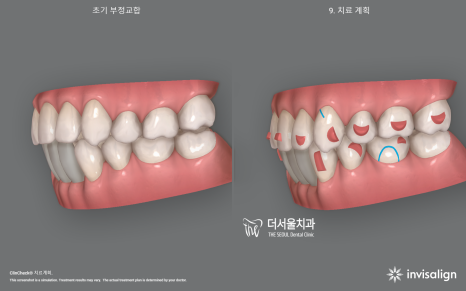

2. 인비절라인 시뮬레이션

시뮬레이션을 영상으로 보니 신기하죠?

인비절라인 클린첵 시뮬레이션을 하면

이렇게 치료 전, 후 를 나눠서 어떤식으로

치아들이 이동이 되면서 빈 틈이 만들어지며

다시 그 빈틈을 메꾸려 다른 치아들을

이동시켜줘야 되는지 술자에게

많은 정보들을 제공합니다.

물론, A.I 기반이라서 최종 수정은

담당 주치의가 직접 진행을 해야 되죠.

이 환자의 경우 임플란트 시술을

해야 되는 상황이라서 우선 임플란트를

심을 수 있는 환경부터 조성해야 됩니다.

이런 것 또한 미리 시뮬레이션에

데이터를 집어넣어서 임플란트의

예상 위치에 따른 교정치료의 종점을

예상할 수 있습니다.